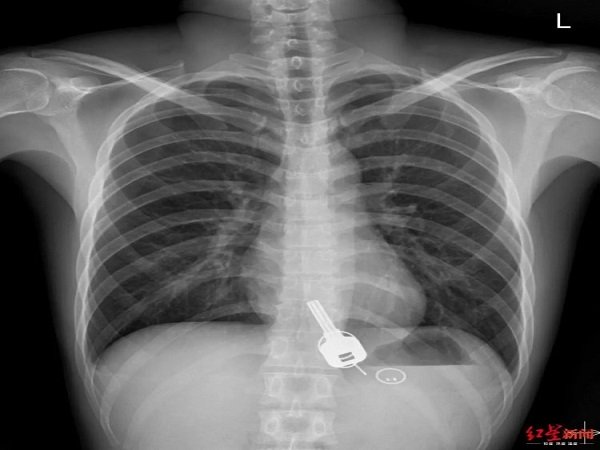

ಕುಡಿದ ಮತ್ತಿನಲ್ಲಿ ಮನೆಯ ಬೀಗದ ಕೈ ನುಂಗಿಬಿಟ್ಟ!

ಮದ್ಯಪಾನ ಮಾಡುವುದು ತುಂಬಾ ಹಾನಿಕಾರಕ ಎಂದು ತಿಳಿದಿದ್ದರೂ ಸಹಿತ ಕೆಲವು ಮಂದಿ ತಪ್ಪದೆ ಇದನ್ನು ಸೇವಿಸುತ್ತಾರೆ. ಇದರಿಂದಾಗಿ ಹಲವಾರು ಸಮಸ್ಯೆಗಳು ಕಾಣಿಸಿಕೊಳ್ಳುವುದು. ಮದ್ಯಪಾನವು ಕೆಲವು ಸಂದರ್ಭಗಳಲ್ಲಿ ಇದು ಅನಾಹುತ ಸೃಷ್ಟಿಸುವುದು. ತಾವು ಏನು ಮಾಡುತ್ತಿದ್ದೇವೆ ಎಂದು ಮದ್ಯಪಾನ ಮಾಡಿದವರಿಗೆ ತಿಳಿದಿರುವುದಿಲ್ಲ. ಅವರು ಈ ಲೋಕದಲ್ಲೇ ಇರುವುದಿಲ್ಲ. ತಮ್ಮ ವರ್ತನೆ ಬಗ್ಗೆ ಅವರಿಗೆ ನಿಯಂತ್ರಣವೇ ಇರದು. ಹೀಗೆ ಇಲ್ಲೊಬ್ಬ ವ್ಯಕ್ತಿ ಅತಿಯಾಗಿ ಮದ್ಯಪಾನ ಮಾಡಿದ ಬಳಿಕ ಮನೆಯ ಬೀಗದ ಕೈಯನ್ನೇ ನುಂಗಿರುವಂತಹ ವಿಚಿತ್ರ ಘಟನೆಯು ನಡೆದಿದೆ.

ಈ ವ್ಯಕ್ತಿಯು ಅತಿಯಾಗಿ ಮದ್ಯಪಾನ ಮಾಡಿದ ಬಳಿಕ ತನ್ನ ಮನೆಯ ಬೀಗದ ಕೈ ಕಳೆದುಕೊಂಡಿದ್ದಾನೆ ಎಂದು ಅದನ್ನು ಹುಡುಕಲು ಆರಂಭಿಸಿದ. ತನ್ನ ಹೊಟ್ಟೆಯಲ್ಲಿ ಏನೋ ತೊಂದರೆ ಕಾಣಿಸುತ್ತಿದ್ದ ಕಾರಣದಿಂದಾಗಿ ಆತ ಹೋಗಿ ವೈದ್ಯರಲ್ಲಿಗೆ ಭೇಟಿ ನೀಡಿದ ಮತ್ತು ಈ ವೇಳೆ ಆತನಿಗೆ ತನ್ನ ತಪ್ಪಿನ ಅರಿವಾಗಿದೆ.

ಚೀನಾದ 26ರ ಹರೆಯದ ಚಾಂಗ್ ಎಂಬ ಹೆಸರಿನ ವ್ಯಕ್ತಿಯೊಬ್ಬ ವಾರಾಂತ್ಯವನ್ನು ತನ್ನ ಸ್ನೇಹಿತರೊಂದಿಗೆ ಕಳೆದಯಲು ಹೋಗಿ ಅತಿಯಾಗಿ ಮದ್ಯಪಾನ ಸೇವಿಸಿದ್ದಾನೆ. ಪಾರ್ಟಿ ಮುಗಿಸಿಕೊಂಡು ಮನೆಗೆ ಬಂದ ವೇಳೆ ಆತನಿಗೆ ಮನೆಯ ಬೀಗದ ಕೈ ಕಳೆದುಕೊಂಡಿರುವ ಬಗ್ಗೆ ಅರಿವಾಗಿದೆ. ಆತ ಮನೆಯ ಒಳಗಡೆ ಇರುವ ಜನರಿಗೆ ಕರೆ ಮಾಡಿ ತಾನು ಬೀಗದ ಕೈ ಕಳೆದುಕೊಂಡಿರುವ ಬಗ್ಗೆ ತಿಳಿಸಿದ್ದಾನೆ.

ಮರುದಿನ ಬೆಳಗ್ಗೆ ಆಲ್ಕೋಹಾಲ್ ನ ನಶೆಯು ಇಳಿದ ಬಳಿಕ ಆತನಿಗೆ ಎದೆಯಲ್ಲಿ ಒಂದು ರೀತಿಯ ನೋವು ಕಾಣಿಸಿಕೊಂಡಿದೆ. ಈ ವೇಳೆ ಆತ ತಕ್ಷಣವೇ ಸಮೀಪದ ಆಸ್ಪತ್ರೆಗೆ ಹೋಗಿ ಪರೀಕ್ಷೆ ಮಾಡಿಸಿಕೊಂಡಿದ್ದಾನೆ.

ವೈದ್ಯರು ಎಕ್ಸ್ ರೇ ಮಾಡಿಸಿದ ಬಳಿಕ ಅವರಿಗೆ ಇದನ್ನು ನೋಡಿ ಒಂದು ಕ್ಷಣ ಆಘಾತವಾಗಿದೆ. ಯಾಕೆಂದರೆ ಚಾಂಗ್ ನ ಅನ್ನನಾಳದಲ್ಲಿ ಬೀಗದ ಕೈ ಸಿಲುಕಿಕೊಂಡಿತ್ತು. ರಾತ್ರಿ ಆತ ತನ್ನ ಮನೆಯ ಬೀಗದ ಕೈ ಕಳೆದುಕೊಂಡಿದ್ದಾಗಿ ಈ ವೇಳೆ ತಿಳಿಸಿದ್ದಾನೆ. ಆದರೆ ಇದು ಆತನ ದೇಹದೊಳಗೆ ಹೇಗೆ ಹೋಯಿತು ಎನ್ನುವ ಬಗ್ಗೆ ಮಾತ್ರ ಆತನಿಗೆ ತಿಳಿದಿರಲಿಲ್ಲ.

ಚಾಂಗ್ ಗೆ ತಾನು ಕೀಯನ್ನು ಹೇಗೆ ನುಂಗಿದ್ದೇನೆ ಎಂದು ತಿಳಿಯದೆ ಇದ್ದ ಕಾರಣದಿಂದಾಗಿ ಇದು ವೈದ್ಯರಿಗೆ ಕೂಡ ದೊಡ್ಡ ರಹಸ್ಯವಾಗಿತ್ತು. ಚಾಂಗ್ ಅತಿಯಾಗಿ ಮದ್ಯಪಾನ ಮಾಡಿದ್ದ ಕಾರಣದಿಂದಾಗಿ ಆತನಿಗೆ ಏನೊಂದು ನೆನಪು ಇರಲಿಲ್ಲ.

ತಕ್ಷಣವೇ ವೈದ್ಯರು ಶಸ್ತ್ರಚಿಕಿತ್ಸೆ ನಡೆಸಿದರು ಮತ್ತು ಕೀಯನ್ನು ನೈಸರ್ಗಿಕ ತಂತ್ರ ಬಳಸಿಕೊಂಡು ತೆಗೆದರೆ ಅದರಿಂದ ಕರುಳಿಗೆ ಹಾನಿಯಾಗುತ್ತಿತ್ತು. ಎಂಡೋಸ್ಕೋಪಿ ಮಾಡಿದರೂ ಅದರಿಂದ ಅನ್ನನಾಳಕ್ಕೆ ಹಾನಿಯಾಗುತ್ತಿತ್ತು. ಇದರಿಂದ ಅವರು ತಕ್ಷಣವೇ ಶಸ್ತ್ರಚಿಕಿತ್ಸೆ ಮಾಡಿ ತೆಗೆಯಲು ಬಯಸಿದರು.

ಸರಿಯಾದ ಸಮಯದಲ್ಲಿ ಕೀಯನ್ನು ಹೊರಗೆ ತೆಗೆದ ಪರಿಣಾಮವಾಗಿ ಚಾಂಗ್ ತುಂಬಾ ಅದೃಷ್ಟವಂತರು ಎಂದು ಪರಿಗಣಿಸಲಾಗಿದೆ. ಆದರೆ ಇದು ದೇಹದ ಒಳಗಡೆ ಹೇಗೆ ಹೋಯಿತು ಎನ್ನುವುದು ಮಾತ್ರ ಈಗಲೂ ದೊಡ್ಡ ರಹಸ್ಯವಾಗಿಯೇ ಇದೆ.